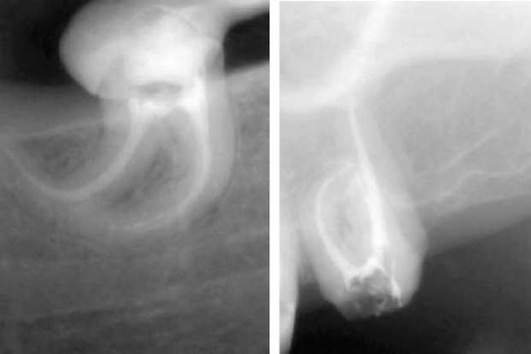

Через 10 с разогрев плаггера активируется на 0,5 с (для отделения его от гут-тaпepчи в апикальной части канала с поворотом на 90°). Далее плаггер выводят из канала с хвостовой частью штифта. Соответствующим ручным плаггером № 1 0,06 конусности Fine (F) разогретая за 0,5 с гуттаперча конденсируется в канале во избежание возникновения пор. Если хвостовая часть гуттаперчевого штифта осталась в канале, ее извлекают с помощью H-файла. Вносят плаггер System B в холодном состоянии до контакта с гуттаперчей и активируют нагрев в течение 0,5 с. Конденсируют разогретую гуттаперчу ручным плаггером № 1 - 0,06 конусности. В результате получают герметично обтурированную апикальную часть канала, дельты, дополнительные и латеральные каналы (рис. 40-10).

pic 0340

Рис. 40-10. Рентгенограмма. Корневые каналы обтурированы с помощью System B.